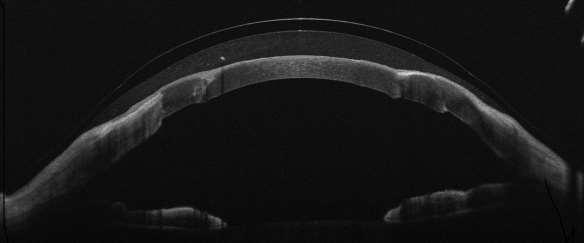

Figura 4. Perfil de adaptación del lente híbrido en ojo izquierdo, tomada con OCT-AS MS39 Syrius.

La evaluación biomicroscópica del lente mostró una adecuada alineación corneo conjuntival sin apoyo en la unión, con bóveda central de 45µm, pericentral de 60µm y prelimbal de 150-107 µm); su asentamiento sobre la superficie ocular fue evaluado en los intervalos de cinco (5) y veinte (20) minutos posteriores a la inserción del lente, y tan sólo al retirarlo se percibió una inusual adherencia que obligó a ajustar el ángulo de la faldilla por uno menos plano.

El reajuste del lente híbrido consistió en aumentar la bóveda entre 20-50µm y la curvatura del faldón a 8.4mm (plana) para alcanzar una profundidad sagital adecuada con menor agarre sobre la zona de aterrizaje evitando, con lo que se buscó reducir la adherencia y facilitar el retiro del lente; posteriormente se calculó la prescripción óptica para visión próxima como sigue a continuación: OD: +1,00Dp (balance) / OI: +2,25-1,00x75° AV VP:20/30.

Figura 5. Adaptación de lente híbrido: detalle OCT de adaptación en OI, tomada con OCT-AS MS39 Syrius.